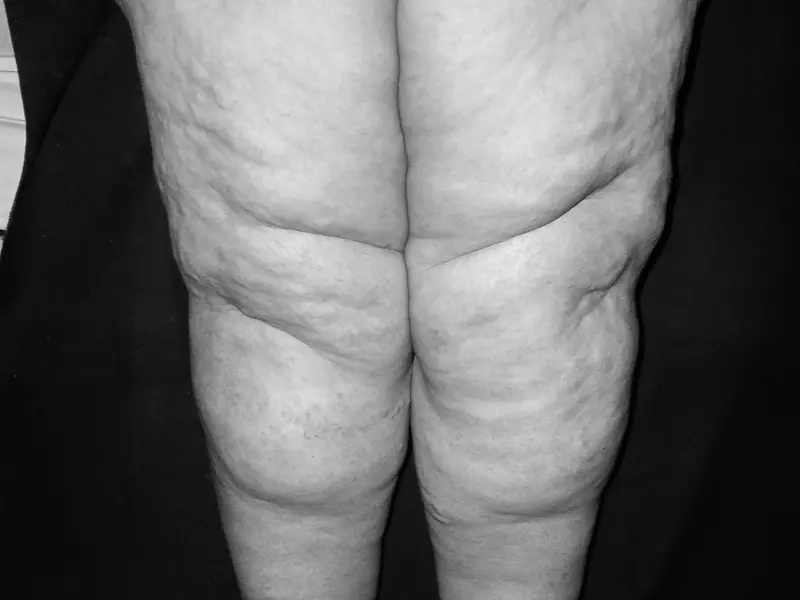

Jest to choroba przewlekła, która charakteryzuje się nadmiernym nagromadzeniem płynu wraz z cząsteczkami białka w przestrzeni pozakomórkowej, prowadzące do wzrostu tkanki tłuszczowej i włóknienia tkanki łącznej1 2. Rozwój LE występuje, kiedy obciążenie przekracza zdolności transportowe układu chłonnego.

Klasyfikacja LE ze względu na przyczynę obejmuje obrzęki pierwotne i wtórne. Pierwotne zaburzenie funkcji układu limfatycznego rozwija się w wyniku patologicznej etiologii wrodzonej i/lub dziedzicznej. Bardziej powszechna postać wtórna jest spowodowana mechaniczną niewydolnością systemu limfatycznego, najczęściej na skutek interwencji chirurgicznej, chemioterapii, napromieniania (włókninie naczyń), urazu, zakażeń, blokad naczyń przez komórki nowotworowe, przewlekłej niewydolności żylnej, otyłości lub bezruchu3 4 5. Obrzęk limfatyczny związany z leczeniem raka piersi (ang. breast cancer related lymphedema – BCRL) stanowi częste powikłanie u kobiet poddanych zabiegom radykalnym. W ostatnich latach techniki te zostały zastąpione oszczędzającymi, a w odniesieniu do rutynowej limfadenektomii wprowadzono biopsję węzła wartowniczego (ang. sentinel lymph node biosy – SLNB). Metoda ta nie przynosi już znamiennego ryzyka pojawienia się LE, gdyż rozpoznawany jest jedynie u 3–7% pacjentek6 7 8. Ryzyko występowania obrzęku limfatycznego ramienia zwiększa się w okresie 2 lat po postawieniu diagnozy lub chirurgii raka piersi. Jego ogólna częstość występowania waha się w granicach 8–56%, w zależności od zakresu chirurgii dołu pachowego i zastosowania leczenia uzupełniającego – radioterapii9. Obrzęk limfatyczny manifestuje się takimi symptomami, jak: wzrost objętości kończyny, dolegliwości bólowe (ból rozpierający, piekący, uczucie ciężkości), upośledzenie funkcji ruchowej stawów kończyny10. Z pewnością jego istota nie ogranicza się wyłącznie do nieestetycznego wyglądu kończyny, ale ma ścisły związek z ubytkami jej funkcji, co przyczynia się do obniżenia jakości życia chorych.